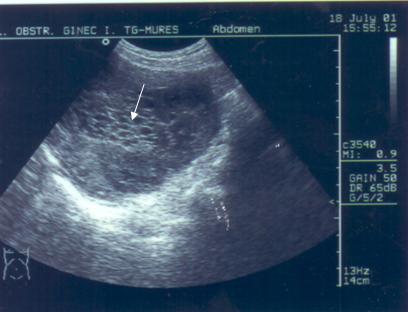

Fig. nr. 9 Sarcina de 5 saptamani la ecografia abdominala.( sacul ovular marcat cu o sageata ) Se remarca retrouterin o formatiune anecogena de peste 5 cm ( chist ovarian marcat cu doua sageti )

Fig. nr. 96. Aceeasi sarcina ca in figura precedenta, retrouterin chist ovarian evident la ecografia transvaginala